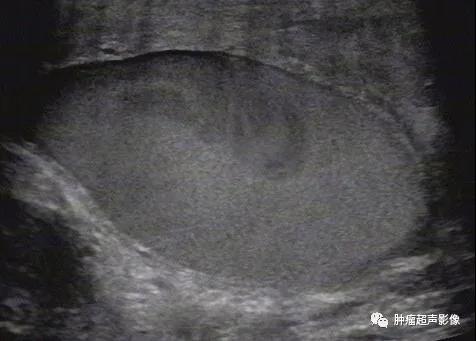

3、睾丸精索鞘膜积液:阴囊内无回声区从三面包绕睾丸,纵切面呈梨形,并向上延伸至精索,其上端较窄。

睾丸精索鞘膜积液